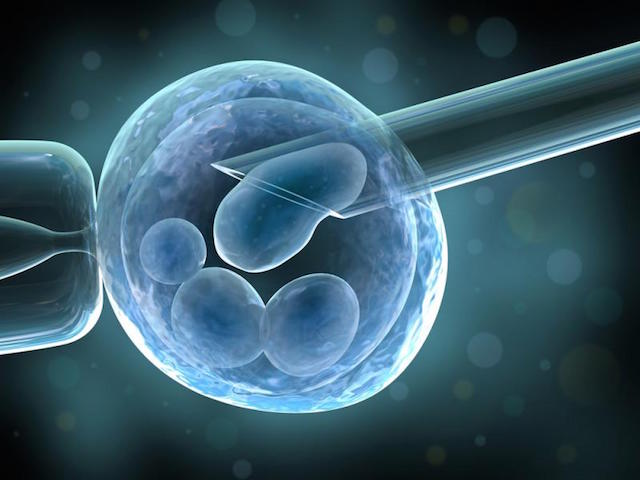

ПовечеАсистирана репродукция по метода ИКСИ (ICSI )

Публикувано на: 22.01.2005 Асистираните репродуктивни технологии са съвкупност от клинични и биологични процедури, които позвол...